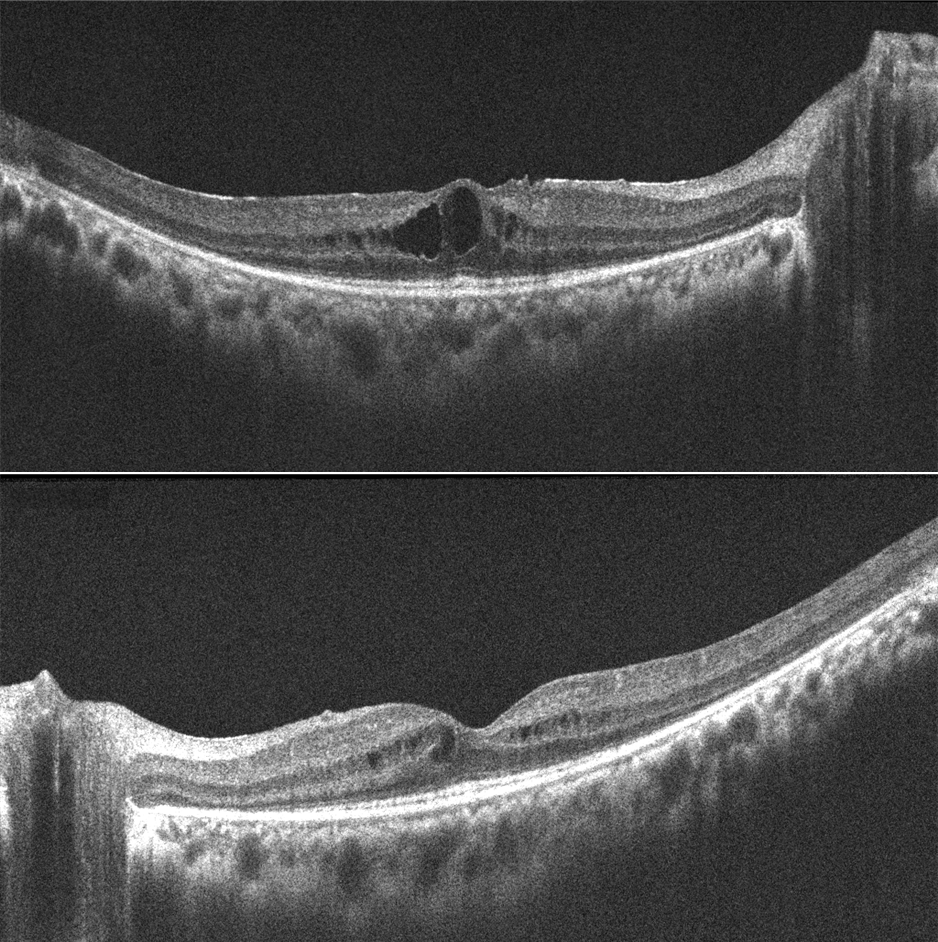

A 26-year-old female patient with cystoid macular edema (CME) secondary to retinitis pigmentosa (RP). Pretreatment OCTs show CME bilaterally. After one month of topical Brinzolamide treatment, visual acuity improved from 20/50 to 20/30 and CME resolved bilaterally.